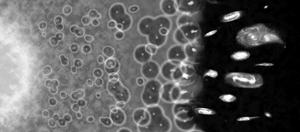

Explican por qué el Universo es transparente a la luz